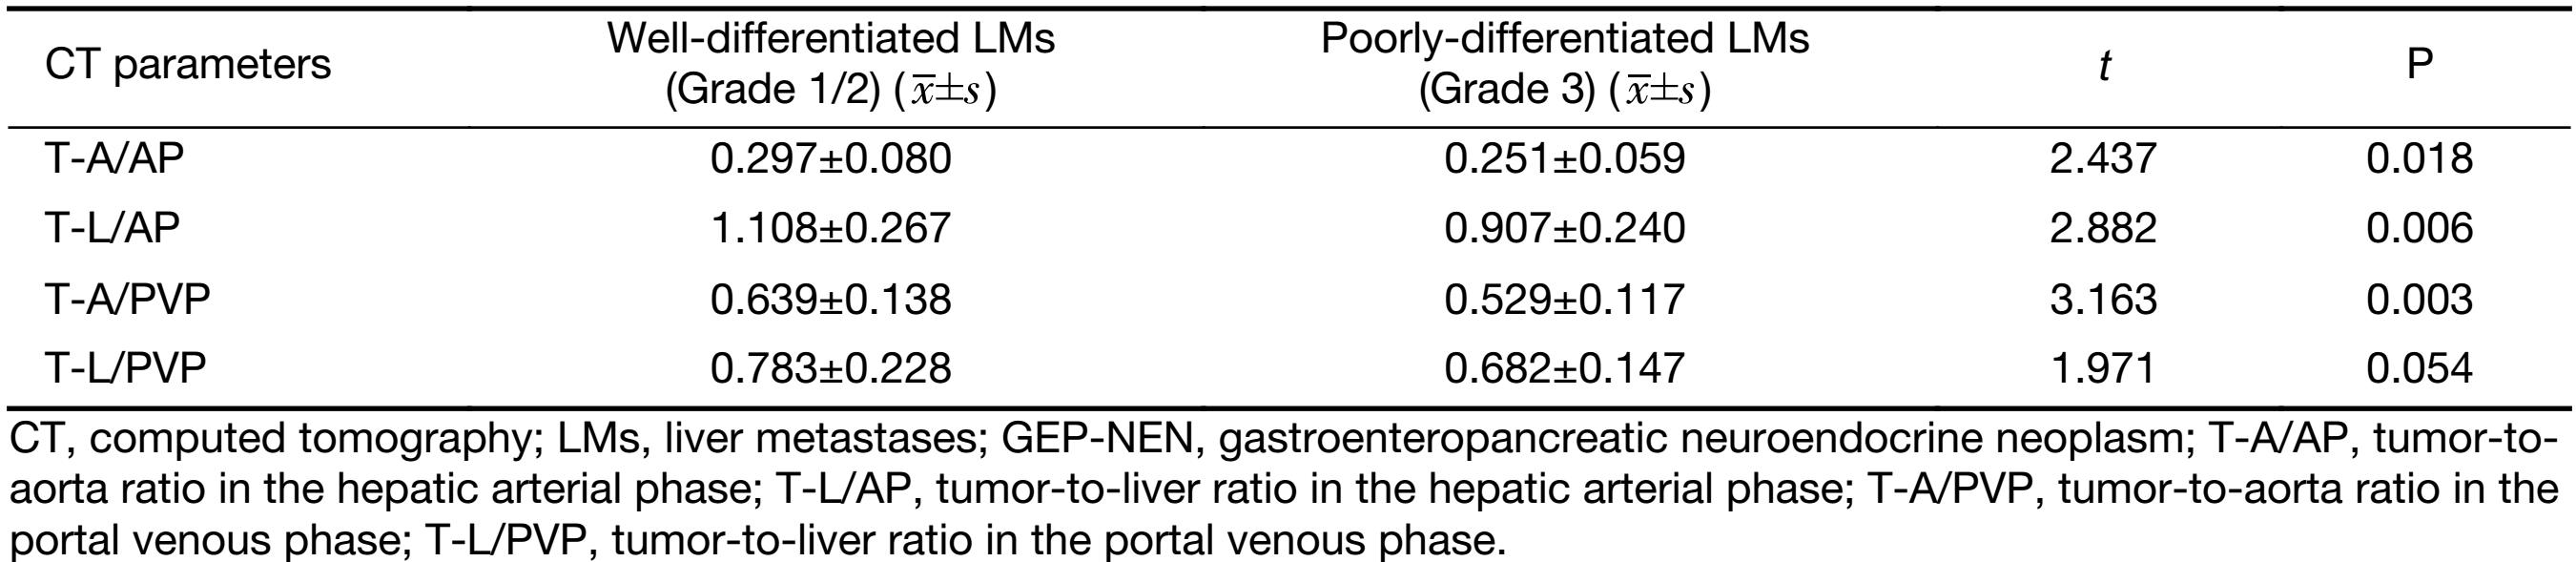

Difference of quantitative CT parameters between LMs of well-differentiated and poorly-differentiated GEP-NENs

The quantitative CT parameters are shown in Table 3. LMs of well-differentiated GEP-NENs were more enhanced than those of poorly-differentiated GEP-NENs. T-A/AP, T-L/AP, and T-A/PVP were significantly higher in LMs of well-differentiated GEP-NENs (all P<0.05) shown by the t-test. Only T-L/PVP was not significantly different between the two groups (P=0.054).